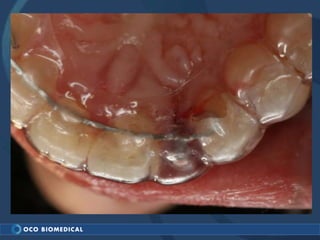

A 3.0mm dental implant was placed to replace congenitally missing maxillary lateral incisors. Dr. Tim Kosinski used a 1.8mm pilot bur and tissue punch to prepare the osteotomy site, then placed the implant by hand and seated it with a torque wrench. After ensuring the implant trajectory was within the restorative envelope, an acrylic coping was placed for temporary fabrication. At the 1 week post-op appointment, excellent soft tissue response and papilla formation were observed, and a final impression was taken to send to the lab for crown fabrication.